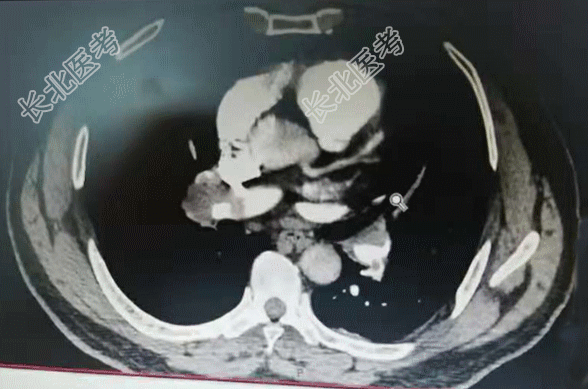

【现病史】2天前,患者无明显诱因出现右侧胸痛不适感,伴呼吸费力。当时无咳嗽、咳痰、发热等症状。以为是劳累导致的症状,经休息后症状缓解不明显,今晨起疼痛症状加重,家属拨打120急救送入我院,急诊科查指脉氧98%,行肺部CTA检查时指脉氧降至92%,肺部CTA显示:肺栓塞。诊断为:肺栓塞。发病以来饮食、睡眠差、小便正常,大便未解,体重无明显变化。

【辅助检查】肺部CTA显示:肺栓塞。心电图:标3、Avf、V₄-V₆导联T波改变。